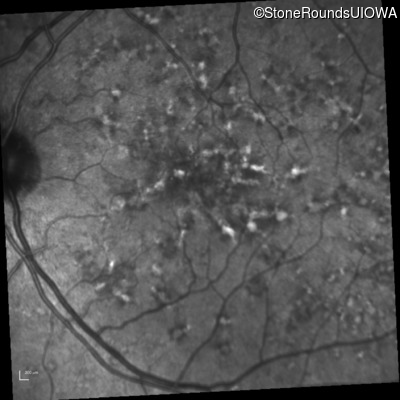

Fluorescein Angiography - Right - 20/40 +2 sc

Exemplar